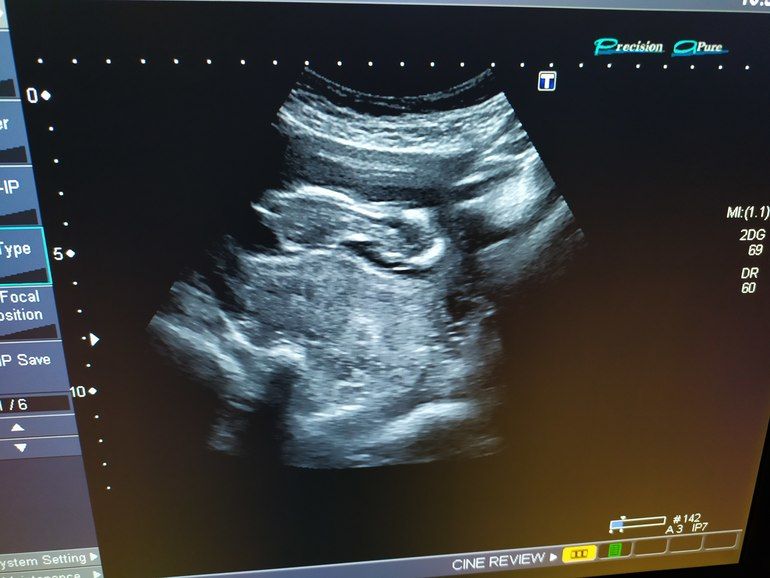

12н6д: первый скрининг💙❤🥰🙏🤗

А мне моя мадам на скрининге хорошо все показала 😎 врач говорит тут сомнений нет. А анализ не так долго ждать осталось, и интриги больше не будет🙈 в остальном шейка мне кажется норм, погрешность измерений может тут сказалась

Наиля , моя любимая доктор прислала мне ответ, что всё отлично, если меня ничего не беспокоит: ЧСС в норме от 120 до 180, и не нужно лезть к человеку, когда он спит))) а гипертонус может быть следствием дел кишечных или реакцией на датчик. И то и другое очень даже да, потому что когда я делала предыдущее УЗИ, доктор сказала, что есть тонус по задней стенке, но это может быть реакцией на датчик. А здесь таких уточнений не делали. А про шейку я забыла спросить, но я так понимаю, до 25 опасений такие шейки вообще ни у кого не вызывают, поэтому нужно просто расслабиться уже😆

Я конечно не спец, но голова по форме как у моих обоих мальчиков была)) сразу обратила внимание ☺️💫 ждём результаты вместе с вами!

Ну слава богу, что все хорошо. А вот я поспорю, у малыша голова более угловатая, нежели у Аурики. У мальчиков реально череп более угловатый. Я своих сравнивала и видно даже в 10 недель было. Так, что ждем анализ😉

Катюнечка Солнышко, я же говорю череп пацанячий прям Изображение